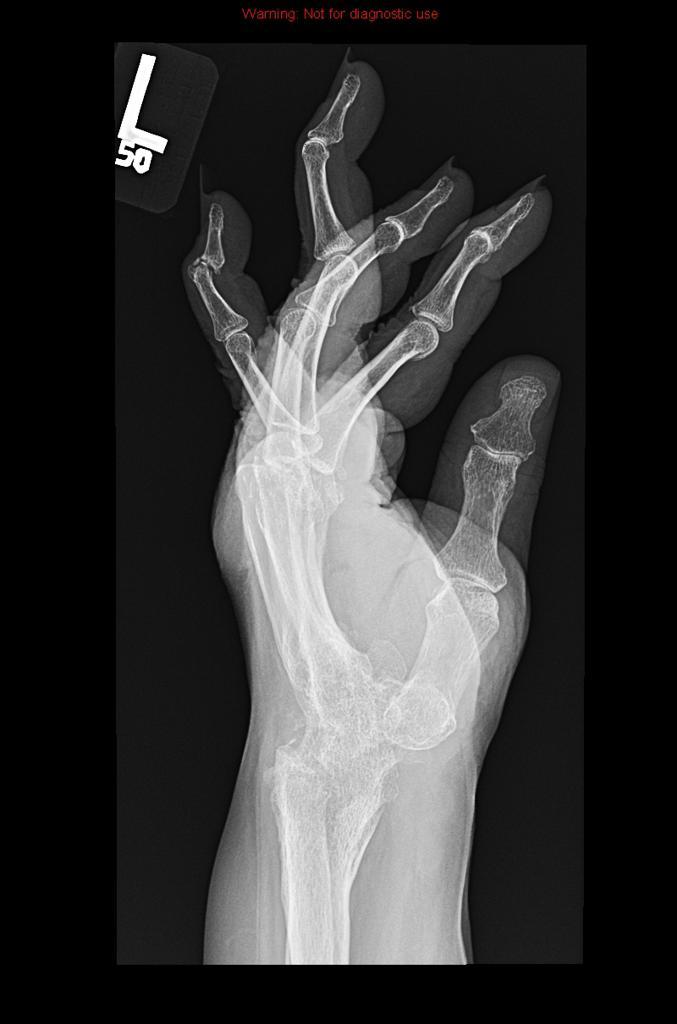

Bad RA in the hands

RA